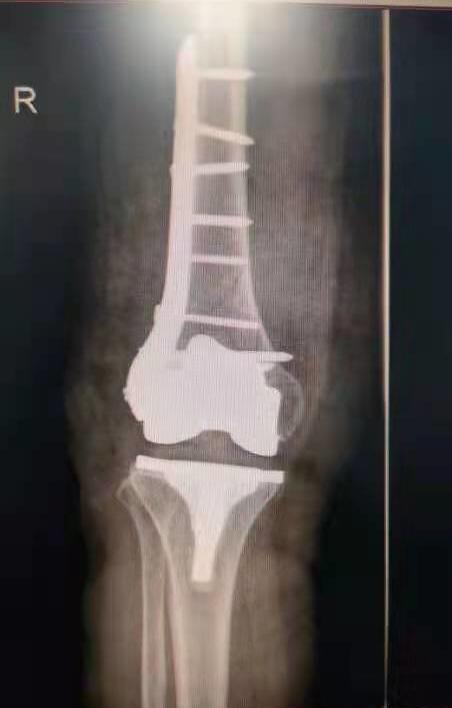

手術前照片

手術后照片